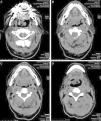

Ante los hallazgos descritos se solicitó una tomografía axial computarizada de cabeza y cuello (fig. 1), se realizó un ultrasonido para la lesión del brazo izquierdo (fig. 2) y se tomó una biopsia escisional en ambas lesiones. El reporte indicó CRCC metastásico en ambas lesiones y, por lo tanto, el paciente fue referido al servicio de oncología quirúrgica. Como estrategia terapéutica se consideró la extirpación de ambos tumores con preservación del órgano afectado. Las piezas quirúrgicas obtenidas se enviaron a estudio anatomopatológico para su diagnóstico definitivo. La tumoración en la base de la lengua presentaba unas dimensiones de 4.5×3.5×2cm, en tanto que las dimensiones de la lesión del músculo bíceps braquial izquierdo fueron de 6×4×4.5cm; los bordes quirúrgicos se encontraban libres de actividad tumoral en ambas lesiones. El reporte definitivo de patología fue de CRCC metastásico para ambas piezas quirúrgicas, confirmando el diagnóstico (fig. 3). El paciente no era candidato a tratamiento sistémico de inmunoterapia adyuvante debido a la presencia de insuficiencia renal.

Tomografía axial computarizada simple de cabeza y cuello. A) Se observa lesión tumoral, localizada en la base de la lengua, de bordes irregulares, multilobulada, heterogénea, que afecta la orofaringe. B-C) Tumoración que muestra un patrón de crecimiento de predominio derecho, infiltrando la amígdala y el pilar amigdalino. D) Se aprecia infiltración del borde libre de la epiglotis.